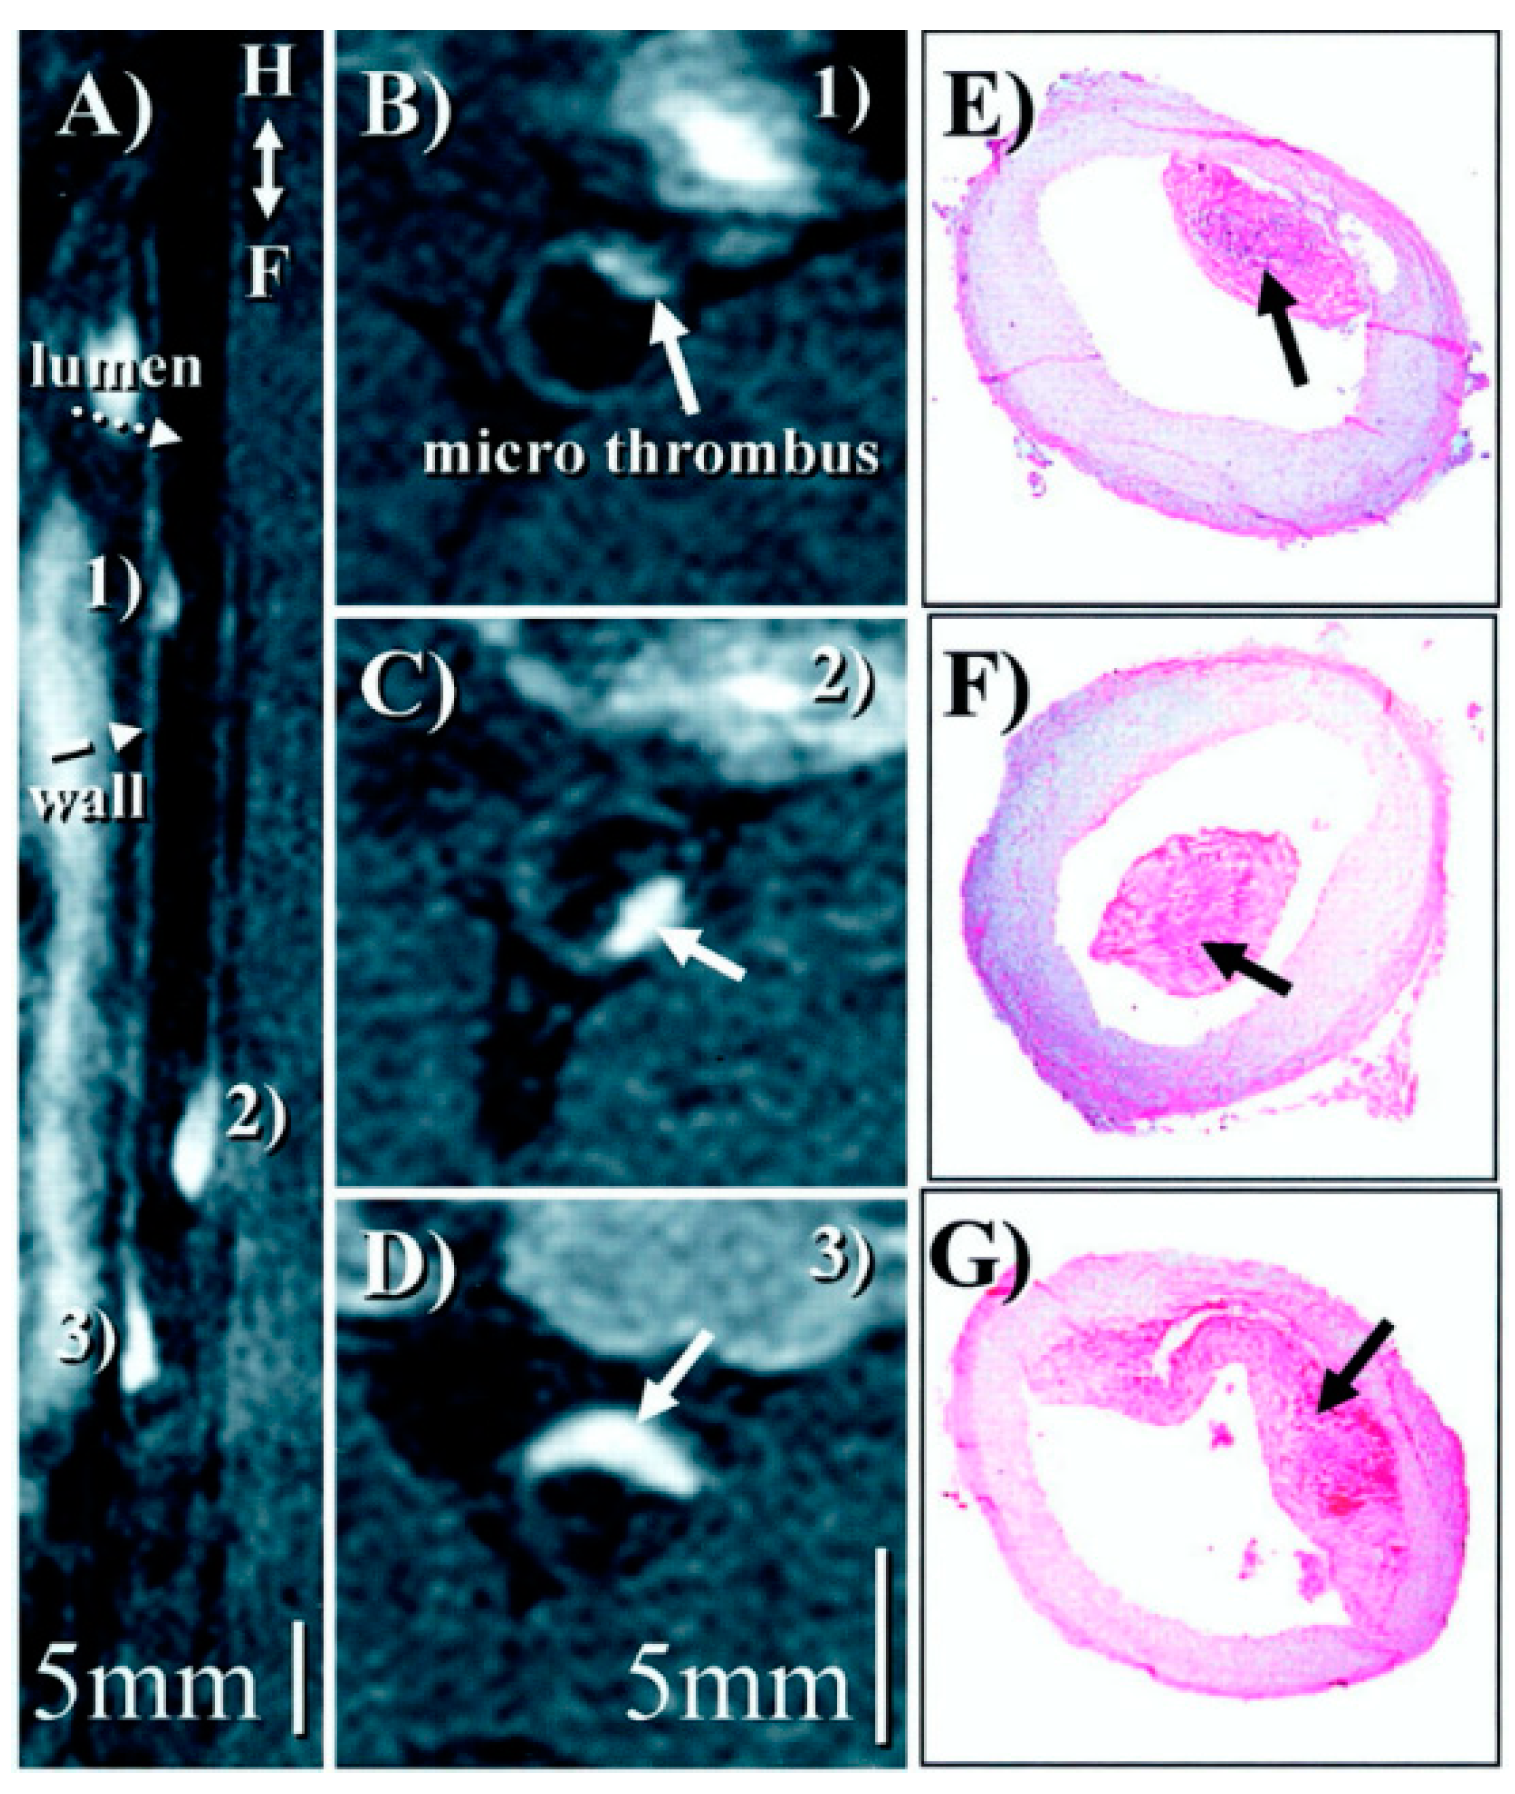

- Botnar, R.M.; Perez, A.S.; Witte, S.; Wiethoff, A.J.; Laredo, J.; Hamilton, J.; Quist, W.; Parsons, E.C.; Vaidya, A.; Kolodziej, A.; et al. In Vivo Molecular Imaging of Acute and Subacute Thrombosis Using a Fibrin-Binding Magnetic Resonance Imaging Contrast Agent. Circulation 2004, 109, 2023–2029. [Google Scholar] [CrossRef]

- Botnar, R.M.; Buecker, A.; Wiethoff, A.J.; Parsons, E.C.; Katoh, M.; Katsimaglis, G.; Weisskoff, R.M.; Lauffer, R.B.; Graham, P.B.; Gunther, R.W.; et al. In Vivo Magnetic Resonance Imaging of Coronary Thrombosis Using a Fibrin-Binding Molecular Magnetic Resonance Contrast Agent. Circulation 2004, 110, 1463–1466. [Google Scholar] [CrossRef] [PubMed]